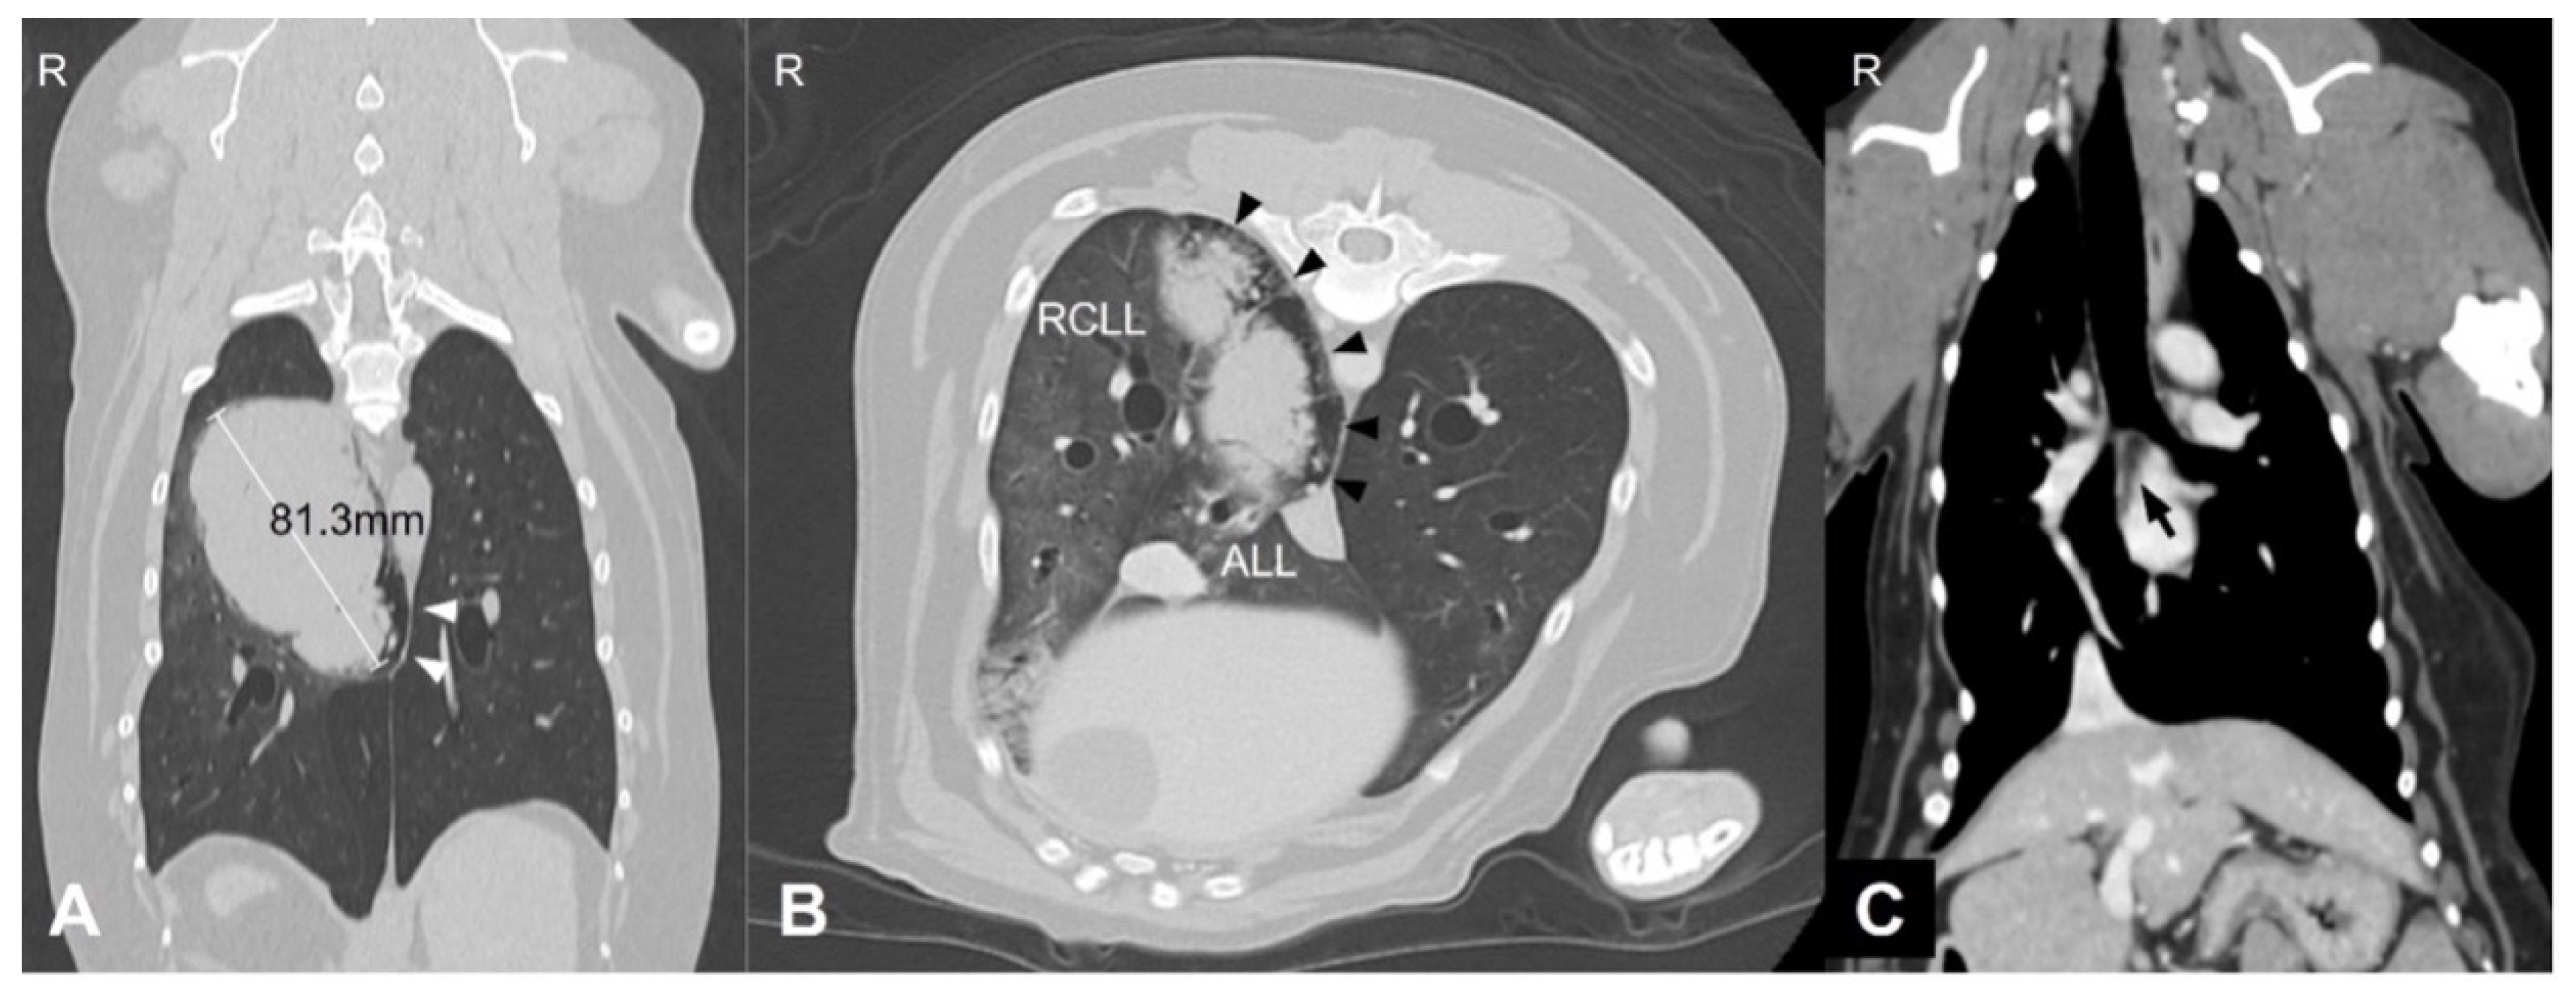

The timeline of clinical events and treatments is summarized in Figure 3. Adverse events (AEs) and disease progression were assessed at baseline and during follow-up evaluations performed every one to two weeks. AEs were graded according to the Veterinary Cooperative Oncology Group Common Terminology Criteria for Adverse Events (VCOG-CTCAE v2.0) [10], and tumor response and disease progression were evaluated using the Response Evaluation Criteria in Solid Tumors (RECIST) [11] based on thoracic radiographs.

Figure 3. Timeline of clinical events, treatments, and tumor responses over a 36-week course. Vinorelbine (orange), piroxicam (green), and cytokine-based NK cell immunotherapy (blue) were administered according to the schedule shown. Carboplatin (red) was initiated upon disease progression. Tumor response was evaluated using RECIST-like criteria (stable disease, green; progressive disease, red). Key clinical events, including splenectomy, hospitalization, and onset of anorexia, are indicated by dotted arrows.